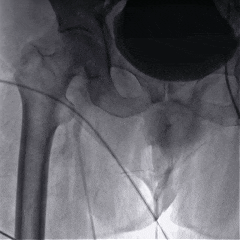

外周入路评估

外周血管检查